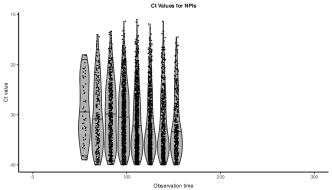

For the scope of this work, we adopt the recent Ct model to evaluate our simulated complex outbreak scenarios. The Ct model estimates epidemiological dynamics from viral load distributions, namely cycle threshold (Ct) values from real-time PCR assays Hay et al. (2021). Ct values represent the viral load in a person at a given point in time, and the distribution of detectable viral loads under random cross-sectional surveillance has been shown to be informative of the epidemic growth rate Hay et al. (2021). Specifically, low Ct values () correspond to high viral loads observed, indicating recent epidemic growth, while high Ct values (; Ct values above 40 cannot be measured due to technical limitations of real-time PCR assays) correspond to low viral loads observed, indicating recent epidemic decline Hay et al. (2021). Still, the Ct model, like other state-of-the-art (SoTA) models for estimating epidemiological dynamics, assumes a single epidemic process that generates the data. We use the Ct model as a demonstration—any epidemiological model can be applied instead—to evaluate an epidemiological model’s robustness in differentiating complex population structures and epidemiological dynamics.

After generating epidemic incidence curves for each of the scenarios using the SEIR model, we simulate observable Ct values under random cross-sectional surveillance, assuming that infected individuals are tested at an unknown point in their infection. The frequency and number of tests simulated are specified in Table S1. To capture the fact that measured Ct values depend on the age of an infection, , we use a previously described model for modal viral load (or Ct) kinetics, , assuming that observed Ct values follow a Gumbel distribution Hay et al. (2021)

| (5) |

where captures the observation that the Ct values exhibit less variability in older infections. We also assume that the parameters underlying the Ct model are known precisely based on previous estimates Hay et al. (2021).